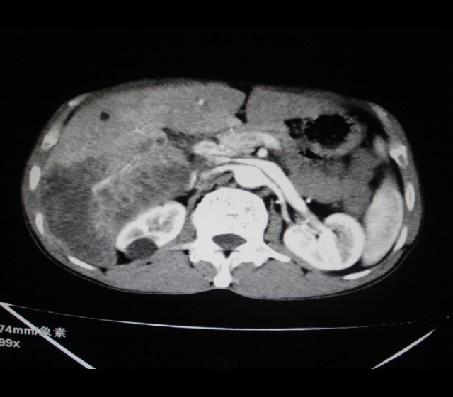

标题: CT24041:肝脏占位,请会诊!

男性,62岁。肝右叶占位,平扫及增强如下,延迟期为15分钟扫描。